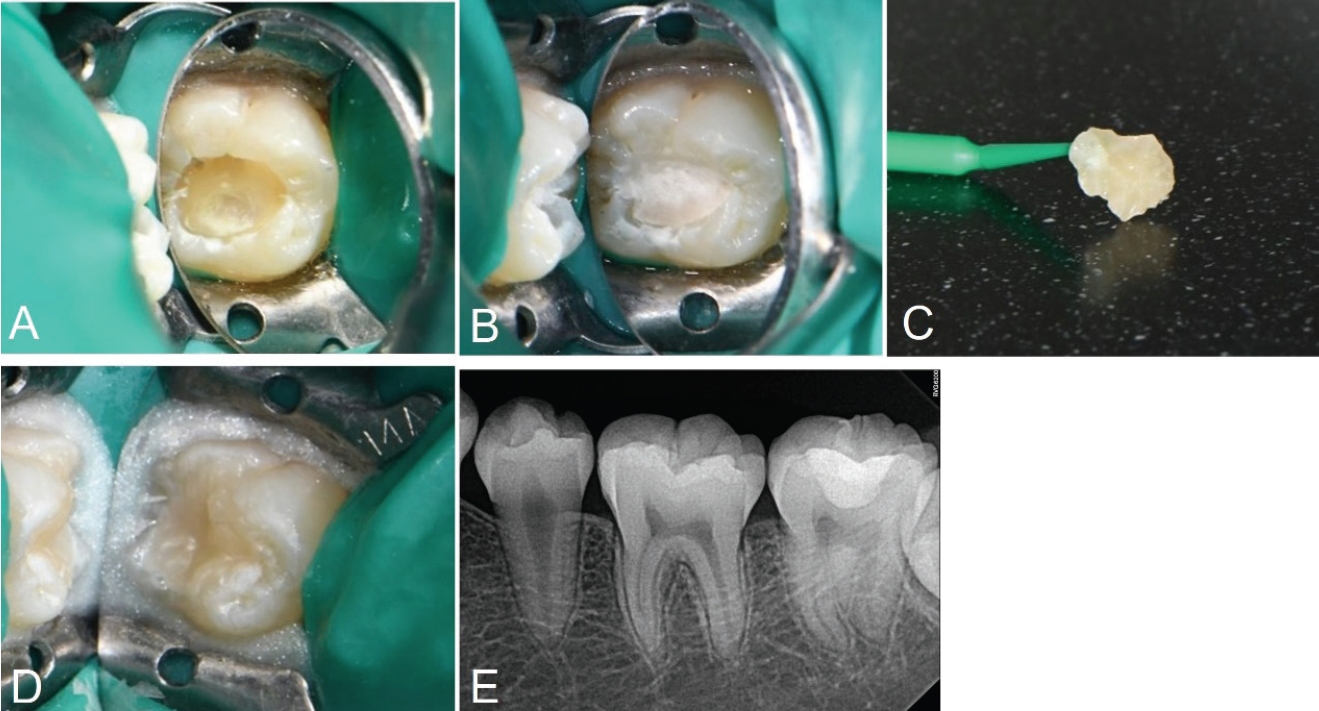

치료 전 1:100000 epinephrine을 포함하는 2% Lidocaine(Yuhan Corporation, Seoul, Korea)으로 우측 하악 구치부 전달마취를 시행하였다. 러버댐을 이용하여 격리를 시행하고 저속핸드피스 및 주수 하에 prophy brush를 사용해 좌측 하악 제2대구치의 교합면을 세정하였다. 이후 유동형 복합레진(Tetric N-Flow, Ivoclar Vivadent, Schaan, Liechtenstein)을 교합면에 적용하고 마이크로브러시의 팁을 손잡이로 사용하기 위해 복합레진에 위치시킨 뒤 광중합하여 스탬프를 형성하였다(Fig. 2C).

A. Caries excavation and cavity preparation is done. B. Base restoration with glass ionomer is done. C. Stamp is obtained using flowable resin and microbrush. D. Photograph after applying stamp on teeth. E. Postoperative periapical radiograph

그 후, 일반적인 와동 형성 프로토콜에 따라 우식 제거를 시행하였다. round diamond bur(BR-31;MANI, Tochigi, Japan)를 이용하여 고속 핸드피스로 주수 하에 우식을 제거하고 class I 형태의 와동을 형성하였다(Fig. 2A). 글라스아이오노머(Ketac Fil Plus Aplicap, 3M ESPE, St. Paul, USA)를 이용해 base 수복을 시행하였다(Fig. 2B). 교합면 와동은 법랑질을 10초간 35% phosphoric acid(Ultra-Etch, Ultradent, South Jordan, USA)로 산부식한 뒤 추가로 상아질에 10초간 더 산부식하고 수세하였다. 약하게 공기를 분사하여 수분을 제거한 뒤 3-step etch-andrinse system인 Adper Scotchbond Multi-Purpose Bond(3M ESPE, St. Paul, USA)의 primer를 microbrush(Microbrush International, Grafton, USA)로 5초간 도포하고 공기 분사 후 adhesive를 microbrush로 5초간 도포하고 공기 분사한 뒤 lightemitting diode(LED) 광중합기(B&Lites, B&L Biotech, Wonju, Korea)로 10초간 중합하였다.

이후 Microhybrid계 복합레진인 Filtek Z250(3M ESPE, St. Paul, USA) 이용해 교합면에서 2mm 아래까지 수복하고 20초간 광중합하였다. 최종 복합레진 적층 전에 다시 복합레진을 적용한 후 테플론 테이프를 교합면에 덮고 마이크로브러시로 만든 스탬프를 정밀하게 위치시켜 가볍게 압력을 주어 눌렀다. 스탬프 및 테플론 테이프를 제거한 뒤 과잉 재료를 레진 기구로 정리한 후 복합레진을 최종 광중합하였다(Fig. 2D). 교합지와 심스탁을 이용한 교합 검사 후 교합 조정을 시행하였다. Sof-lex spiral(3M ESPE, St. Paul, USA)로 수복물 연마를 시행하였다.